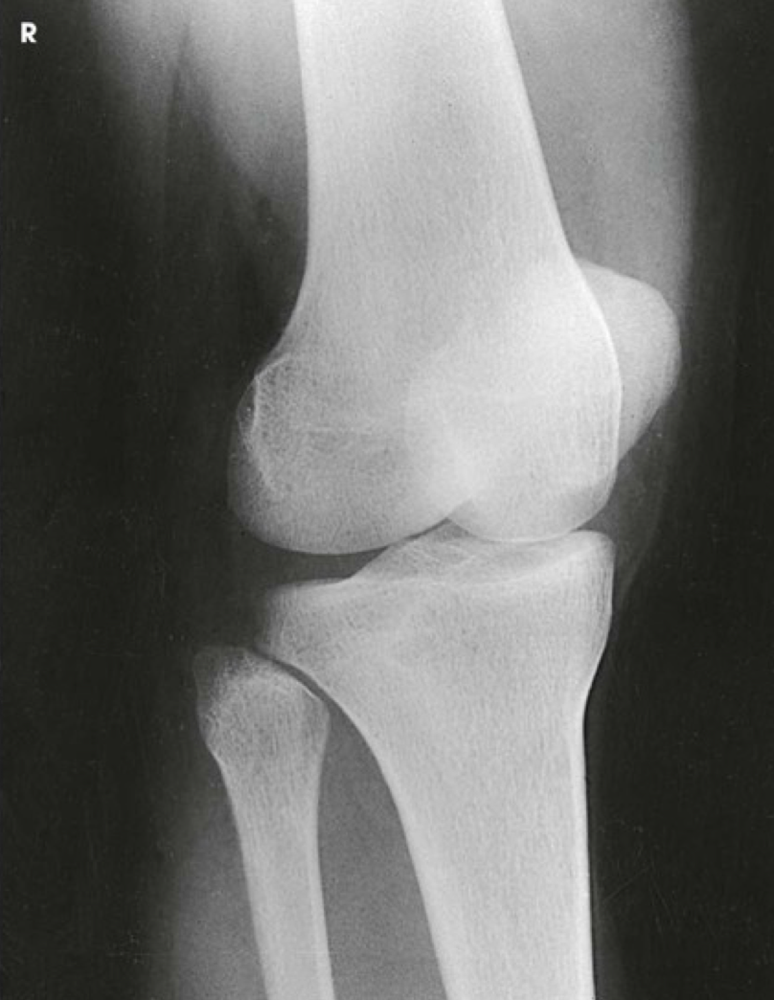

Question

Label the image

Image:

15e1ea34-f491-43b4-b8c9-d5e76573228a (image/png)

Answer

femur

tibial plateau

tibia

fibula